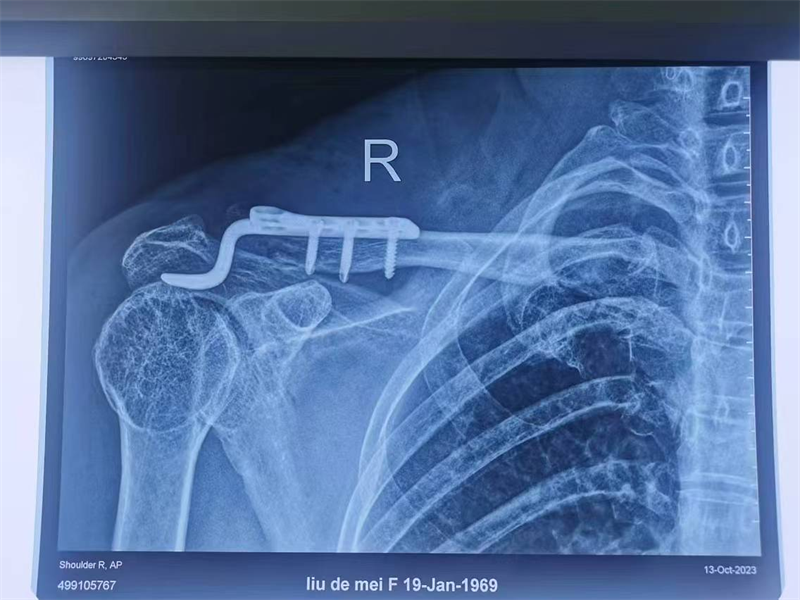

近期,寿光和信医院骨外科采取肩锁关节脱位切开复位袢钛板内固定术,一锚双袢固定,为肩锁关节脱位患者提供了一种全新的治疗选择。

传统一般都是使用锁骨钩钢板治疗肩锁关节脱位,术中将尖钩紧贴肩峰下缘插入肩锁关节后方的肩峰下,3~4枚螺钉将钢板固定于锁骨,可获得良好的疗效。但钢板内固定术后最常见的并发症是肩部疼痛、肩峰下黏连导致肩关节术后活动受限及钩尖所致的肩峰切割,还需要二次手术取出钢板等,给患者带来很多不便。

肩锁关节脱位是创伤骨科的一种常见疾病,而肩锁关节脱位切开复位袢钛板内固定术则为这些患者带来了曙光。术后功能良好,肩锁关节脱位Ⅲ度新鲜损伤生物重建有优势,美容缝合,不用二期取出内固定,简单、实用、美观、功能良好,比钩钢板固定有很大优势。通过及时的治疗和正确的康复措施,患者完全可以告别肩锁关节疼痛带来的困扰,重新拥有健康和快乐的生活。